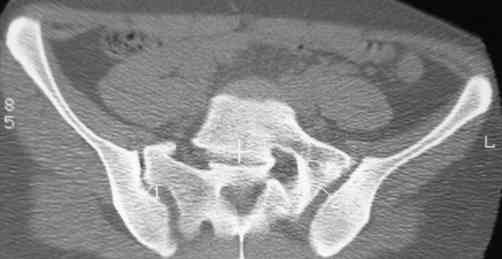

В больнице вправили вывих бедра, три недели на вытяжении. Беспокоят боли в левом тазобедренном суставе и левом крестцово-подвздошном сочленении. Ходит с тростью. Снимок - в приложении. Направил на КТ, заключение: разрыв симфиза и левого крестцово-подвздошного сочленения, переломы крыши и заднего края вертлужной впадины, горизонтальной ветви лонной кости слева.

Уважаемый д-р Булахтин, на мой взгляд единственное повреждение требующее синтеза - застарелый разрыв лона. Низкий перелом передней колонны безопасен, повреждения свода не вижу, неясно что было сзади (скорее боковая масса)лучше сделать обзорный снимок прямой и Inlet.

Очень похоже на повреждение от бокового сжатия.

Признаков разрыва сочленения не вижу, м.б. контрлатеральный перелом боковой массы.

Если был задний вывих, то повреждение должно локализоваться сзади. В данном случае перелом спереди, как результат сдавления лонного сочленения.

Синтез лонного сочленения восстановит стабильность тазового кольца.